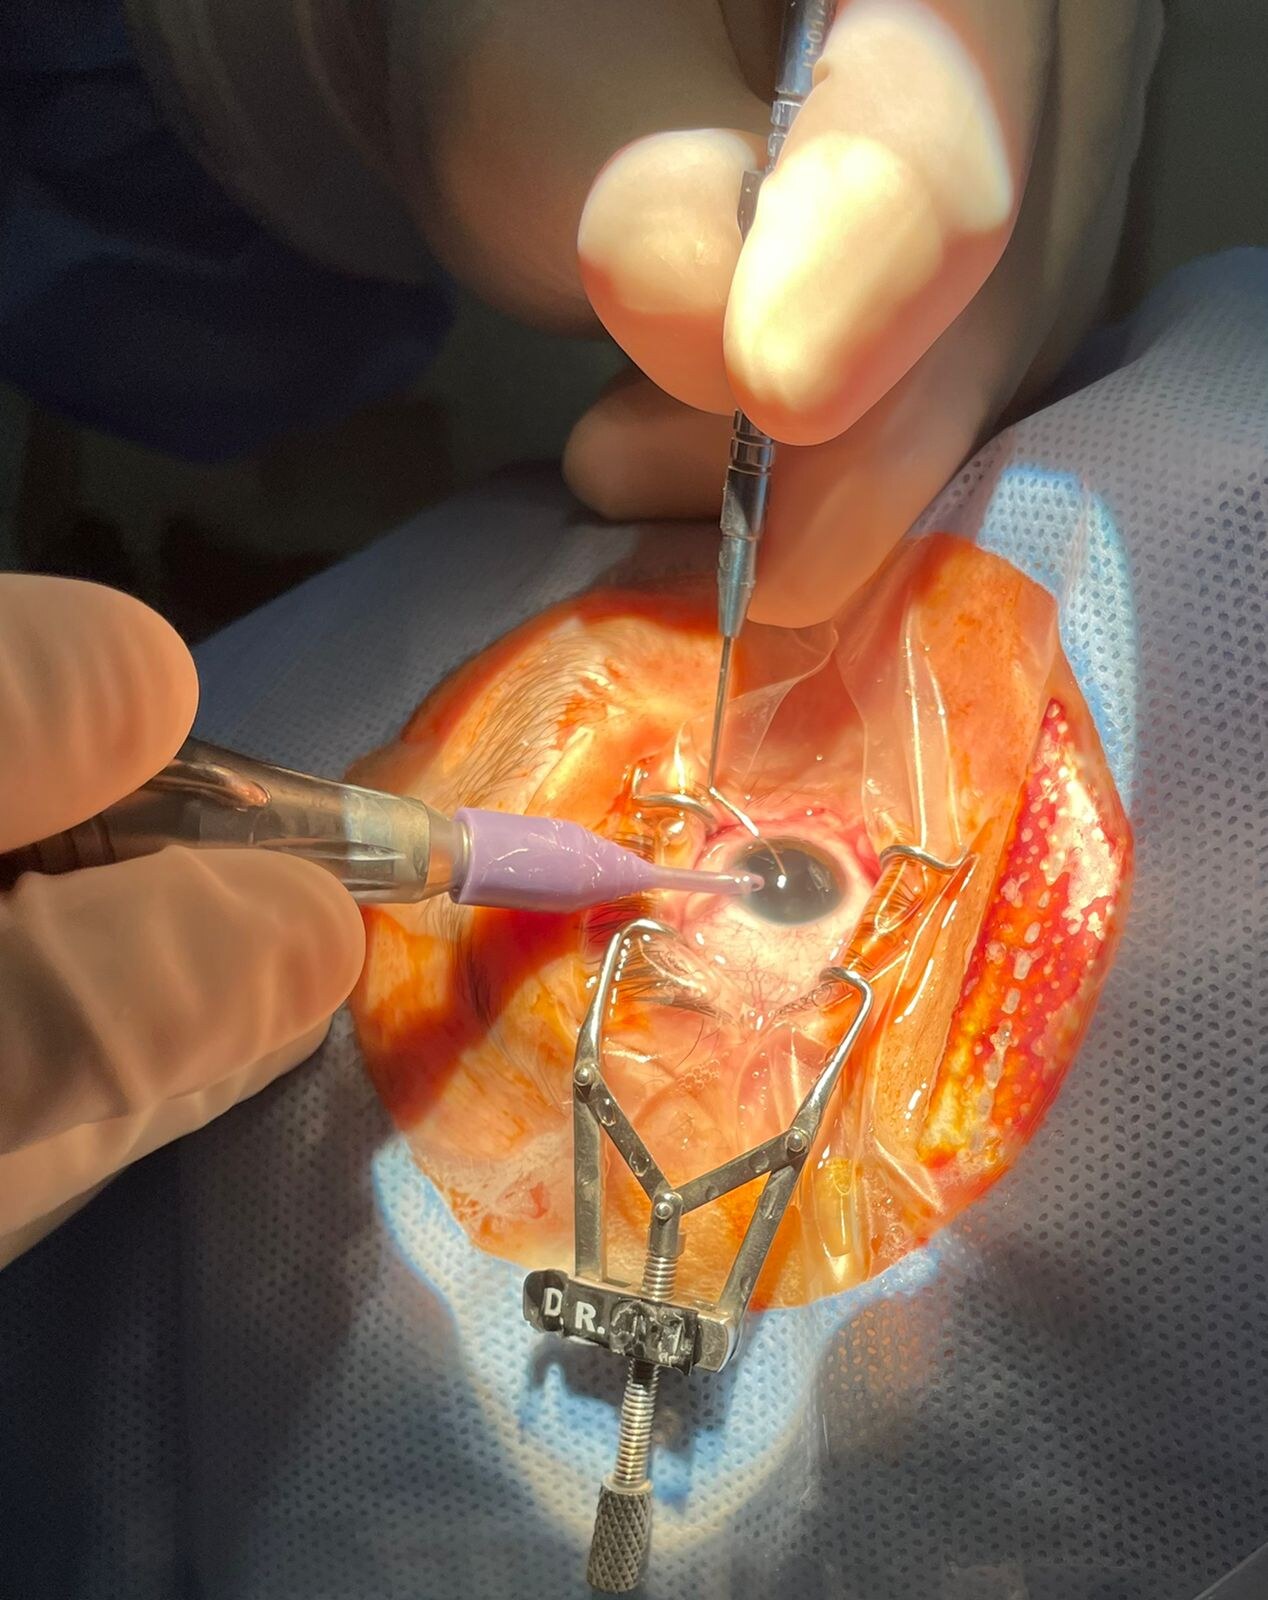

Cirurgia de Catarata Implante de Lente Intraocular

Consiste na retirada do cristalino (lente natural do olho),para implante de uma lente intraocular avaliada, caso a caso, para obter o melhor resultado visual.

A catarata é removida por por facoemulsificacão ou por femtosegundo (cirurgia à laser). A escolha da técnica a ser empregada depende de vários fatores que são orientados pelo cirurgião ao paciente que será operado.